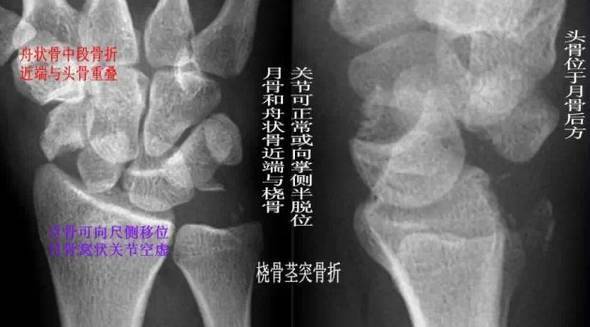

(4)经舟骨月骨周围脱位:表现为月骨周围脱位伴舟骨骨折,且骨折远段随头骨向后脱位,而骨折近段与桡骨、月骨关系保持正常。

下一页 股骨转子间骨折常见分型